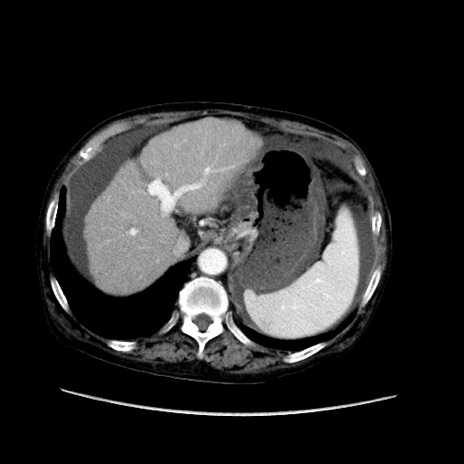

症例31(横断像)

【症例】80歳代 女性

【主訴】腹部膨満感

【現病歴】他院にて肝硬変にてフォロー中。1週間前から便秘、腹部膨満感、臍部腫瘤あり受診となる。

【既往歴】肝硬変

【身体所見】腹部膨隆あり、皮膚変化なし、疼痛なし。

【データ】WBC 4600、CRP 0.25